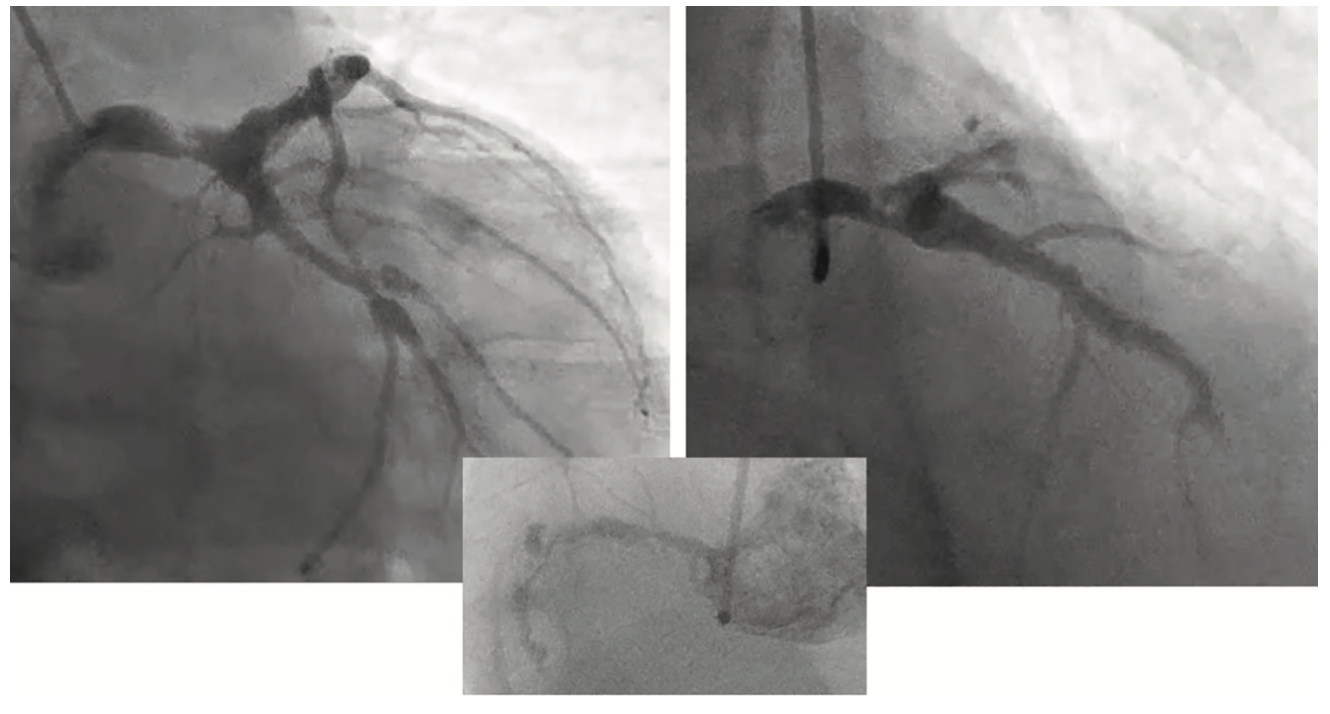

A 72-year-old patient with stable exertional angina on appropriate medical therapy was brought to the cath lab after a positive preoperative screening stress test (electrocardiogram [ECG] ST depressions) for cataracts. (Usually, cataract surgery doesn’t get screening stress tests, but sometimes it is done.) On angiography, we found an 80% irregular, ulcerated-appearing left main artery narrowing and total right coronary artery (RCA) with left-to-right collaterals (Figure 1). Echocardiography showed a left ventricular ejection fraction (LVEF) of 45%. After discussions with the patient and surgical colleagues at our nearby referring hospital, we planned to transfer this patient urgently after the procedure for coronary artery bypass graft (CABG) surgery. However, there were no beds available for surgery at any of our three potential referral sites. This delay in needed care could be a bigger problem if the patient destabilizes and needs urgent revascularization. Fortunately, and for a majority of our patients, we are able to treat the patient conservatively with heparin and anti-ischemic meds until a bed opens up.

Our lab is a hospital-based PCI/electrophysiology lab without SOS. Here is what we did. Although the patient was very stable after the angiogram, given the ulcerated image of the left main (LM), we had concern that urgent surgery was needed (flow chart, Figure 2). We found that we could not transfer the patient that day due to lack of outside bed availability. We admitted him to the intermediate monitored care unit, initiated heparin infusion, and continued his home medications while awaiting a surgical bed at one of our referral CABG facilities. It took 2 days to transfer the patient. He then had his surgery without any complications and was discharged home.